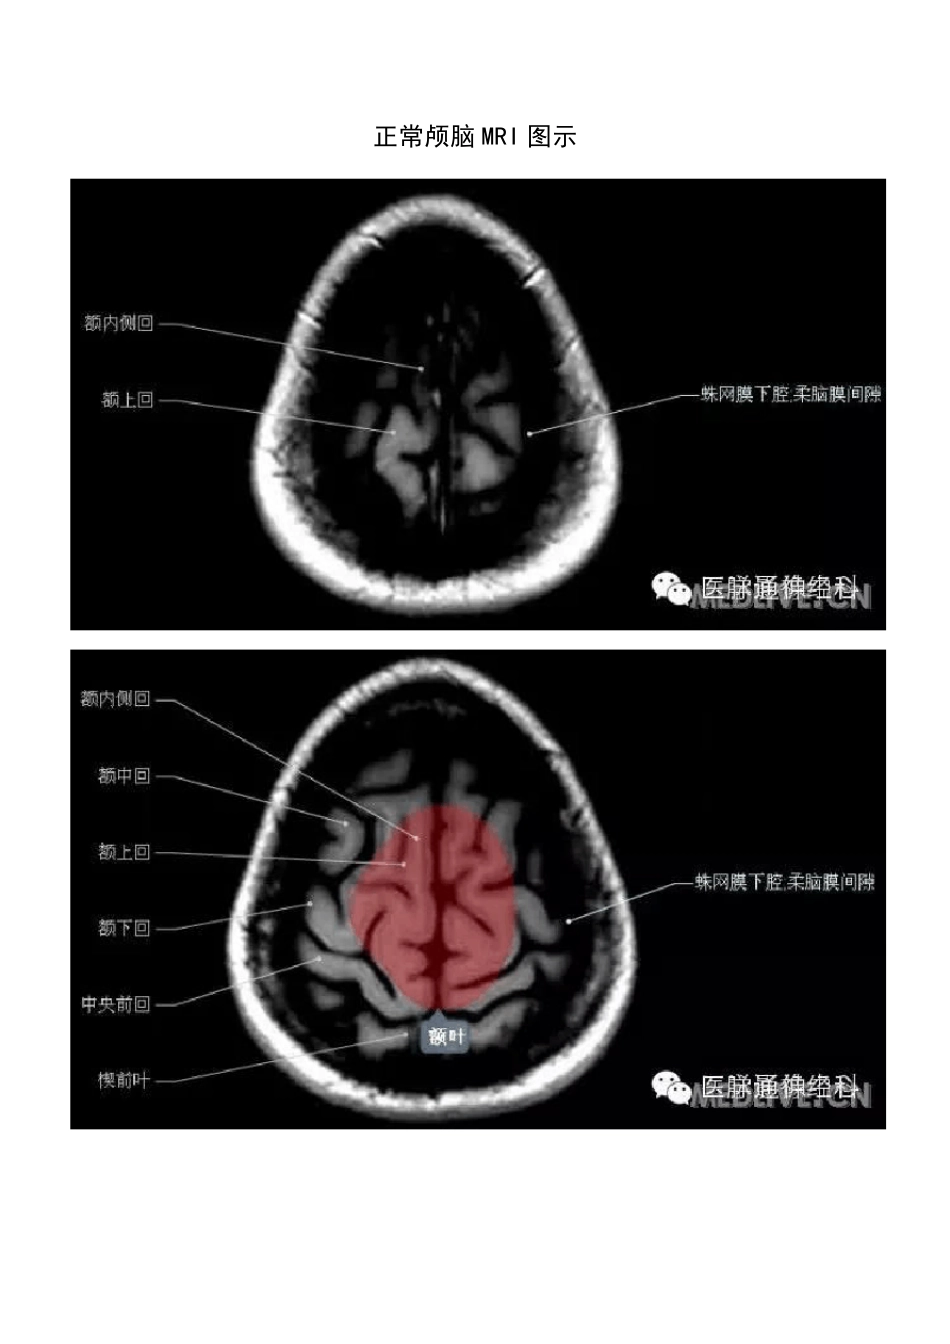

正常颅脑MRI 图示

正常颅脑磁共振图示